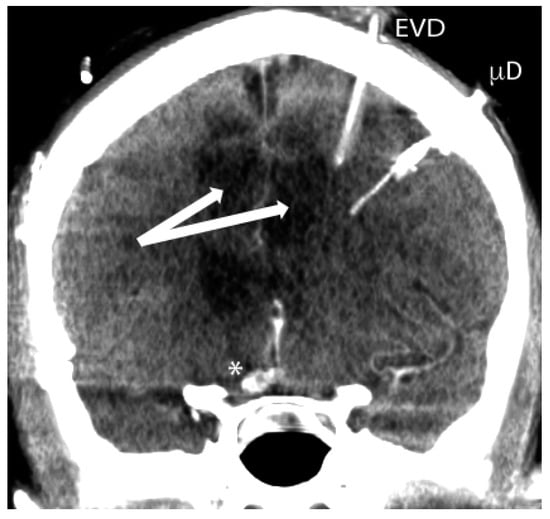

| Intracranial pressure (ICP) monitor | Available as ventricular or parenchymal probe | Well-established in traumatic brain injury; Ventricular drain allows removal of cerebrospinal fluid for ICP therapy/labs | Invasive monitor, potential risk of infection, hardware malfunction |

| Microdialysis | Intraparenchymal probe obtains dialysate for lab assays | Informative of cerebral microenvironment and metabolic state; special lab assays possible | Invasive monitor, potential risk of infection, hardware malfunction, results potentially not reflective of entire brain |

| PbtO2 | Intraparenchymal probe measures partial pressure of oxygen | Enables targeted therapy | Invasive monitor, potential risk of infection, hardware malfunction, results potentially not reflective of entire brain |